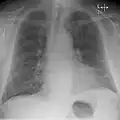

Kerley B lines in radiograph of acute cardiac decompensation. The short, horizontal lines can be found everywhere in the right lung.

Chronic stable heart failure may easily decompensate (fail to meet the body's metabolic needs). This most commonly results from a concurrent illness (such as myocardial infarction (a heart attack) or pneumonia), abnormal heart rhythms, uncontrolled hypertension, or a person's failure to maintain a fluid restriction, diet, or medication.[50]

Chest radiograph of a lung with distinct Kerley B lines, as well as an enlarged heart (as shown by an increased cardiothoracic ratio, cephalization of pulmonary veins, and minor pleural effusion as seen for example in the right horizontal fissure. Yet, no obvious lung edema is seen. Overall, this indicates intermediate severity (stage II) heart failure.

Chest X-rays are frequently used to aid in the diagnosis of CHF. In a person who is compensated, this may show cardiomegaly (visible enlargement of the heart), quantified as the cardiothoracic ratio (proportion of the heart size to the chest). In left ventricular failure, evidence may exist of vascular redistribution (upper lobe blood diversion or cephalization), Kerley lines, cuffing of the areas around the bronchi, and interstitial edema. Ultrasound of the lung may also detect Kerley lines.[73]